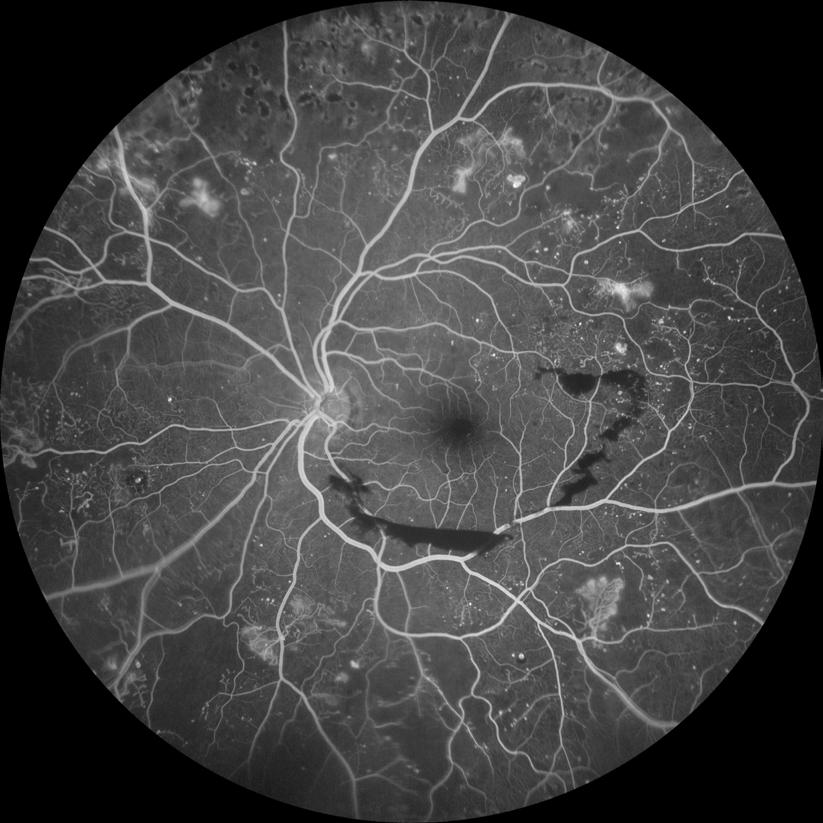

Purtscher Retinopathy in Nonhuman Primate

Purtscher retinopathy is often associated with blunt trauma, but may also occur in other systemic conditions like acute pancreatitis, hemolytic uremic syndrome, and renal failure where acute complementmediated leukoembolization likely contributes to the typ-

ical appearance of cotton-wool spots, retinal hemorrhage, optic disc edema, and inner retinal whitening. Affected patients also experience reduced vision acuity with possibilities of eyesight recovery, depending on the disease progression in other affected organs.1 However, the

a c d e b

Figure 1: Multimodal imaging of NHP Purtscher-like retinopathy. (a) External photographs, (b) color fundus photographs (FP), (c) spectral-domain optical coherence tomography (OCT), (d) early-phase fluorescein angiography (FA), and (e) late-phase FA of the left and right eyes of the affected macaque during the clinical eye examination at 16 years old. Abbreviations: OD, right eye; OS, left eyes. Scale bars, 200µm.

pathogenesis of Purtscher retinopathy remains unclear. Here, we report a unique case of Purtscher retinopathy in a nonhuman primate (NHP) with multiple body system complications found at necropsy.

A 16-year-old female rhesus macaque (Macaca mulatta) was diagnosed with severe Purtscher-like retinopathy during a routine eye examination. Intraocular pressures were 7 and 8 mmHg for the right and left eye, respectively, but with no other anterior segment abnormalities (Figure 1a). Fundus examination and photography revealed diffuse cotton-wool spots bilaterally extending across both macula and periphery, which corresponded to the nerve fiber layer (NFL) thickening on optical coherence tomography (OCT) suggesting NFL infarction (Figures 1b and 1c). OCT also showed severe retinal edema with intraretinal and subretinal fluid which was more prominent in the right eye (Figure 1c). Intraretinal hyperreflective foci were also apparent on OCT, suggesting intracellular infiltrates that are likely inflammatory in nature. Early-phase fluorescein angiography (FA) of the right eye showed choroidal filling defects suggestive of

patchy choroidal ischemia while late-phase FA exhibited multiple foci of leakage, suggestive of increased retinal vessel permeability in both eyes (Figures 1d and 1e). The affected macaque died one month after the eye examination. At necropsy, the cause of the sudden death was attributed to left ventricular hypertrophy. Damage to the kidneys and the lungs were found with glomerulosclerosis and interstitial fibrosis in the kidneys along with tubular casts, blood, and high levels of protein found in the urine. Acute pulmonary edema was also noted. Furthermore, the tricavitary fibrinous effusion and focal acute myocardial necrosis suggested that this animal was septic although the source of infection was unknown. We hypothesize that the sepsis and renal failure were the cause of the Purtscher-like retinopathy in nonhuman primates.